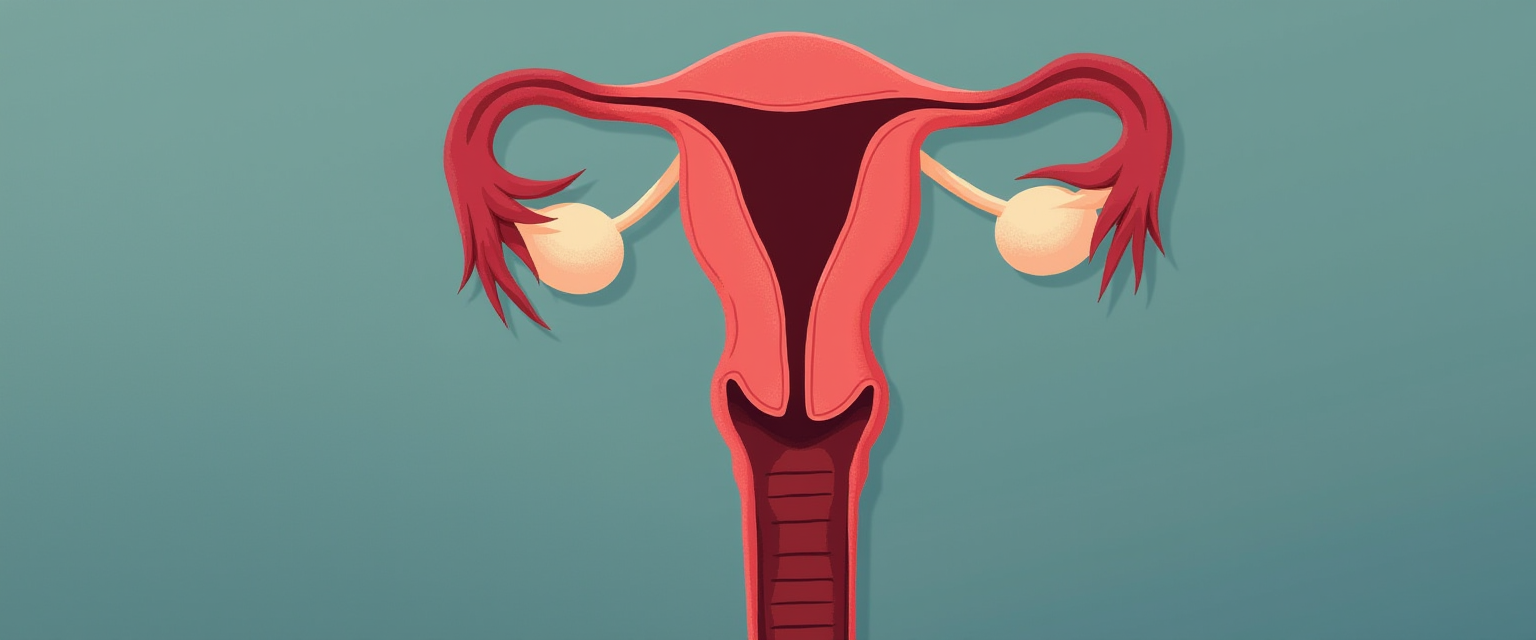

Пациентка «Н», возраст 41 год, в анамнезе 2 родов, кормление грудью двоих детей по 11 месяцев.

Пациентка 68 лет обратилась к хирургу с жалобами на увеличение размеров живота и снижение массы тела.